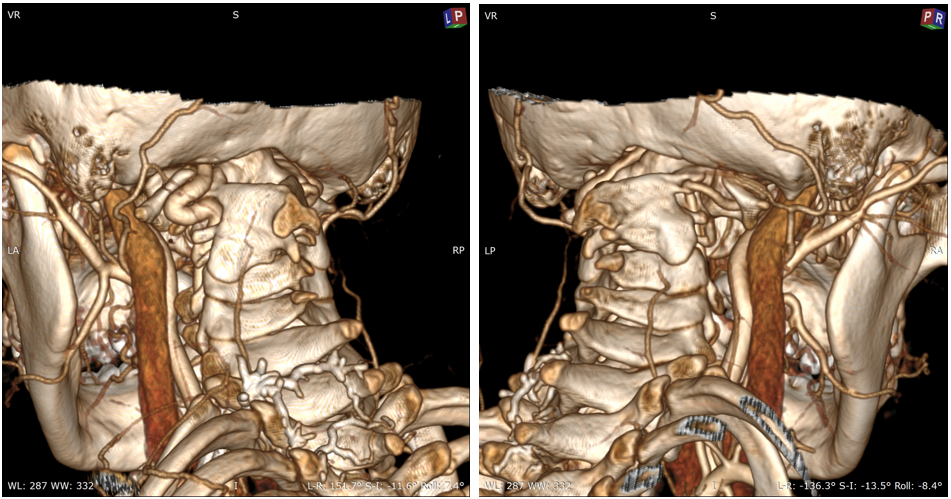

女,13岁,154cm,57kg

• 6个月前病人出现颈部活动受限,3个月前出现左手力弱

影像资料:

• 齿状突小体

• 寰枢椎脱位

• 后路关节松解寰枢椎复位内固定融合术

• 前路关节松解,后路寰枢椎复位内固定融合术

• 前路TARP技术

• 前路齿状突切除,后路内固定术